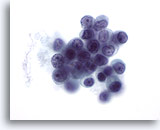

Figure 50

Breast FNA, Lobular carcinoma.

Intracytoplasmic vacuoles are commonly seen in lobular carcinoma aspirates, as seen in the single cell in the upper left of the field. Vacuoles are not exclusive to lobular carcinoma as they may also be seen in ductal carcinoma. 60x

Figure 50

Breast FNA, Lobular carcinoma.

Intracytoplasmic vacuoles are commonly seen in lobular carcinoma aspirates, as seen in the single cell in the upper left of the field. Vacuoles are not exclusive to lobular carcinoma as they may also be seen in ductal carcinoma.

60x